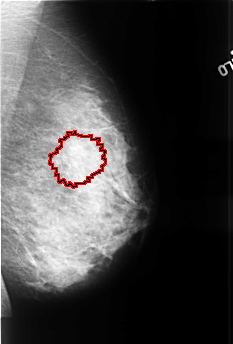

FILE: B_3390_1.LEFT_MLO.OVERLAY

TOTAL_ABNORMALITIES 1

ABNORMALITY 1

LESION_TYPE MASS SHAPE ARCHITECTURAL_DISTORTION MARGINS SPICULATED

ASSESSMENT 4

SUBTLETY 2

PATHOLOGY MALIGNANT

TOTAL_OUTLINES 1

BOUNDARY